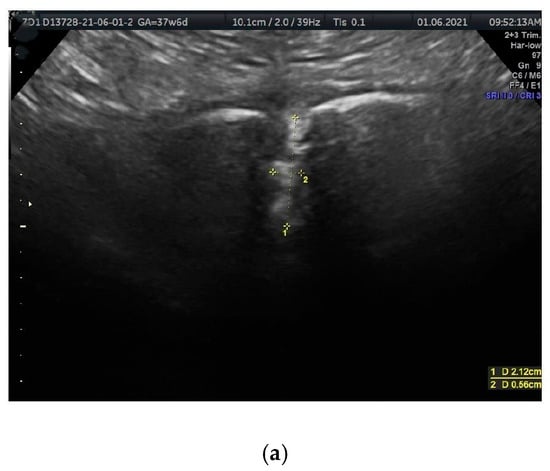

Ultrasound visualization was performed using coronal (frontal) planes, with the transducer directed from the superior margin to the inferior margin of the anterior pelvic bony wall, parallel to the anterior abdominal wall. In this plane, the PS resembles a funnel that gradually narrows inferiorly (Figure 1a,b and Figure 2a,b). The US scan consists of a wider, quadrangular part, which we propose to name the PS entry, and the proper, rectangular PS disc. The PS entry is bordered superiorly by the intertubercular line, which runs between the right and left PTs. The superior border of the PS disc forms the inferior border of this entry. The lateral borders, both right and left, are defined by lines connecting the PTs to the lateral-superior angles of the disc.

(a,b). The sonographic transducer was placed on the superior border of the anterior bony wall of the pelvis, parallel to the anterior abdominal wall. (a) Measured parameters displayed in the sonographic scan. Distance 1 = PSw (PS width); distance 2 = PSd (PS depth). (b) A corresponding schematic drawing exemplifying the measurements of PS parameters.